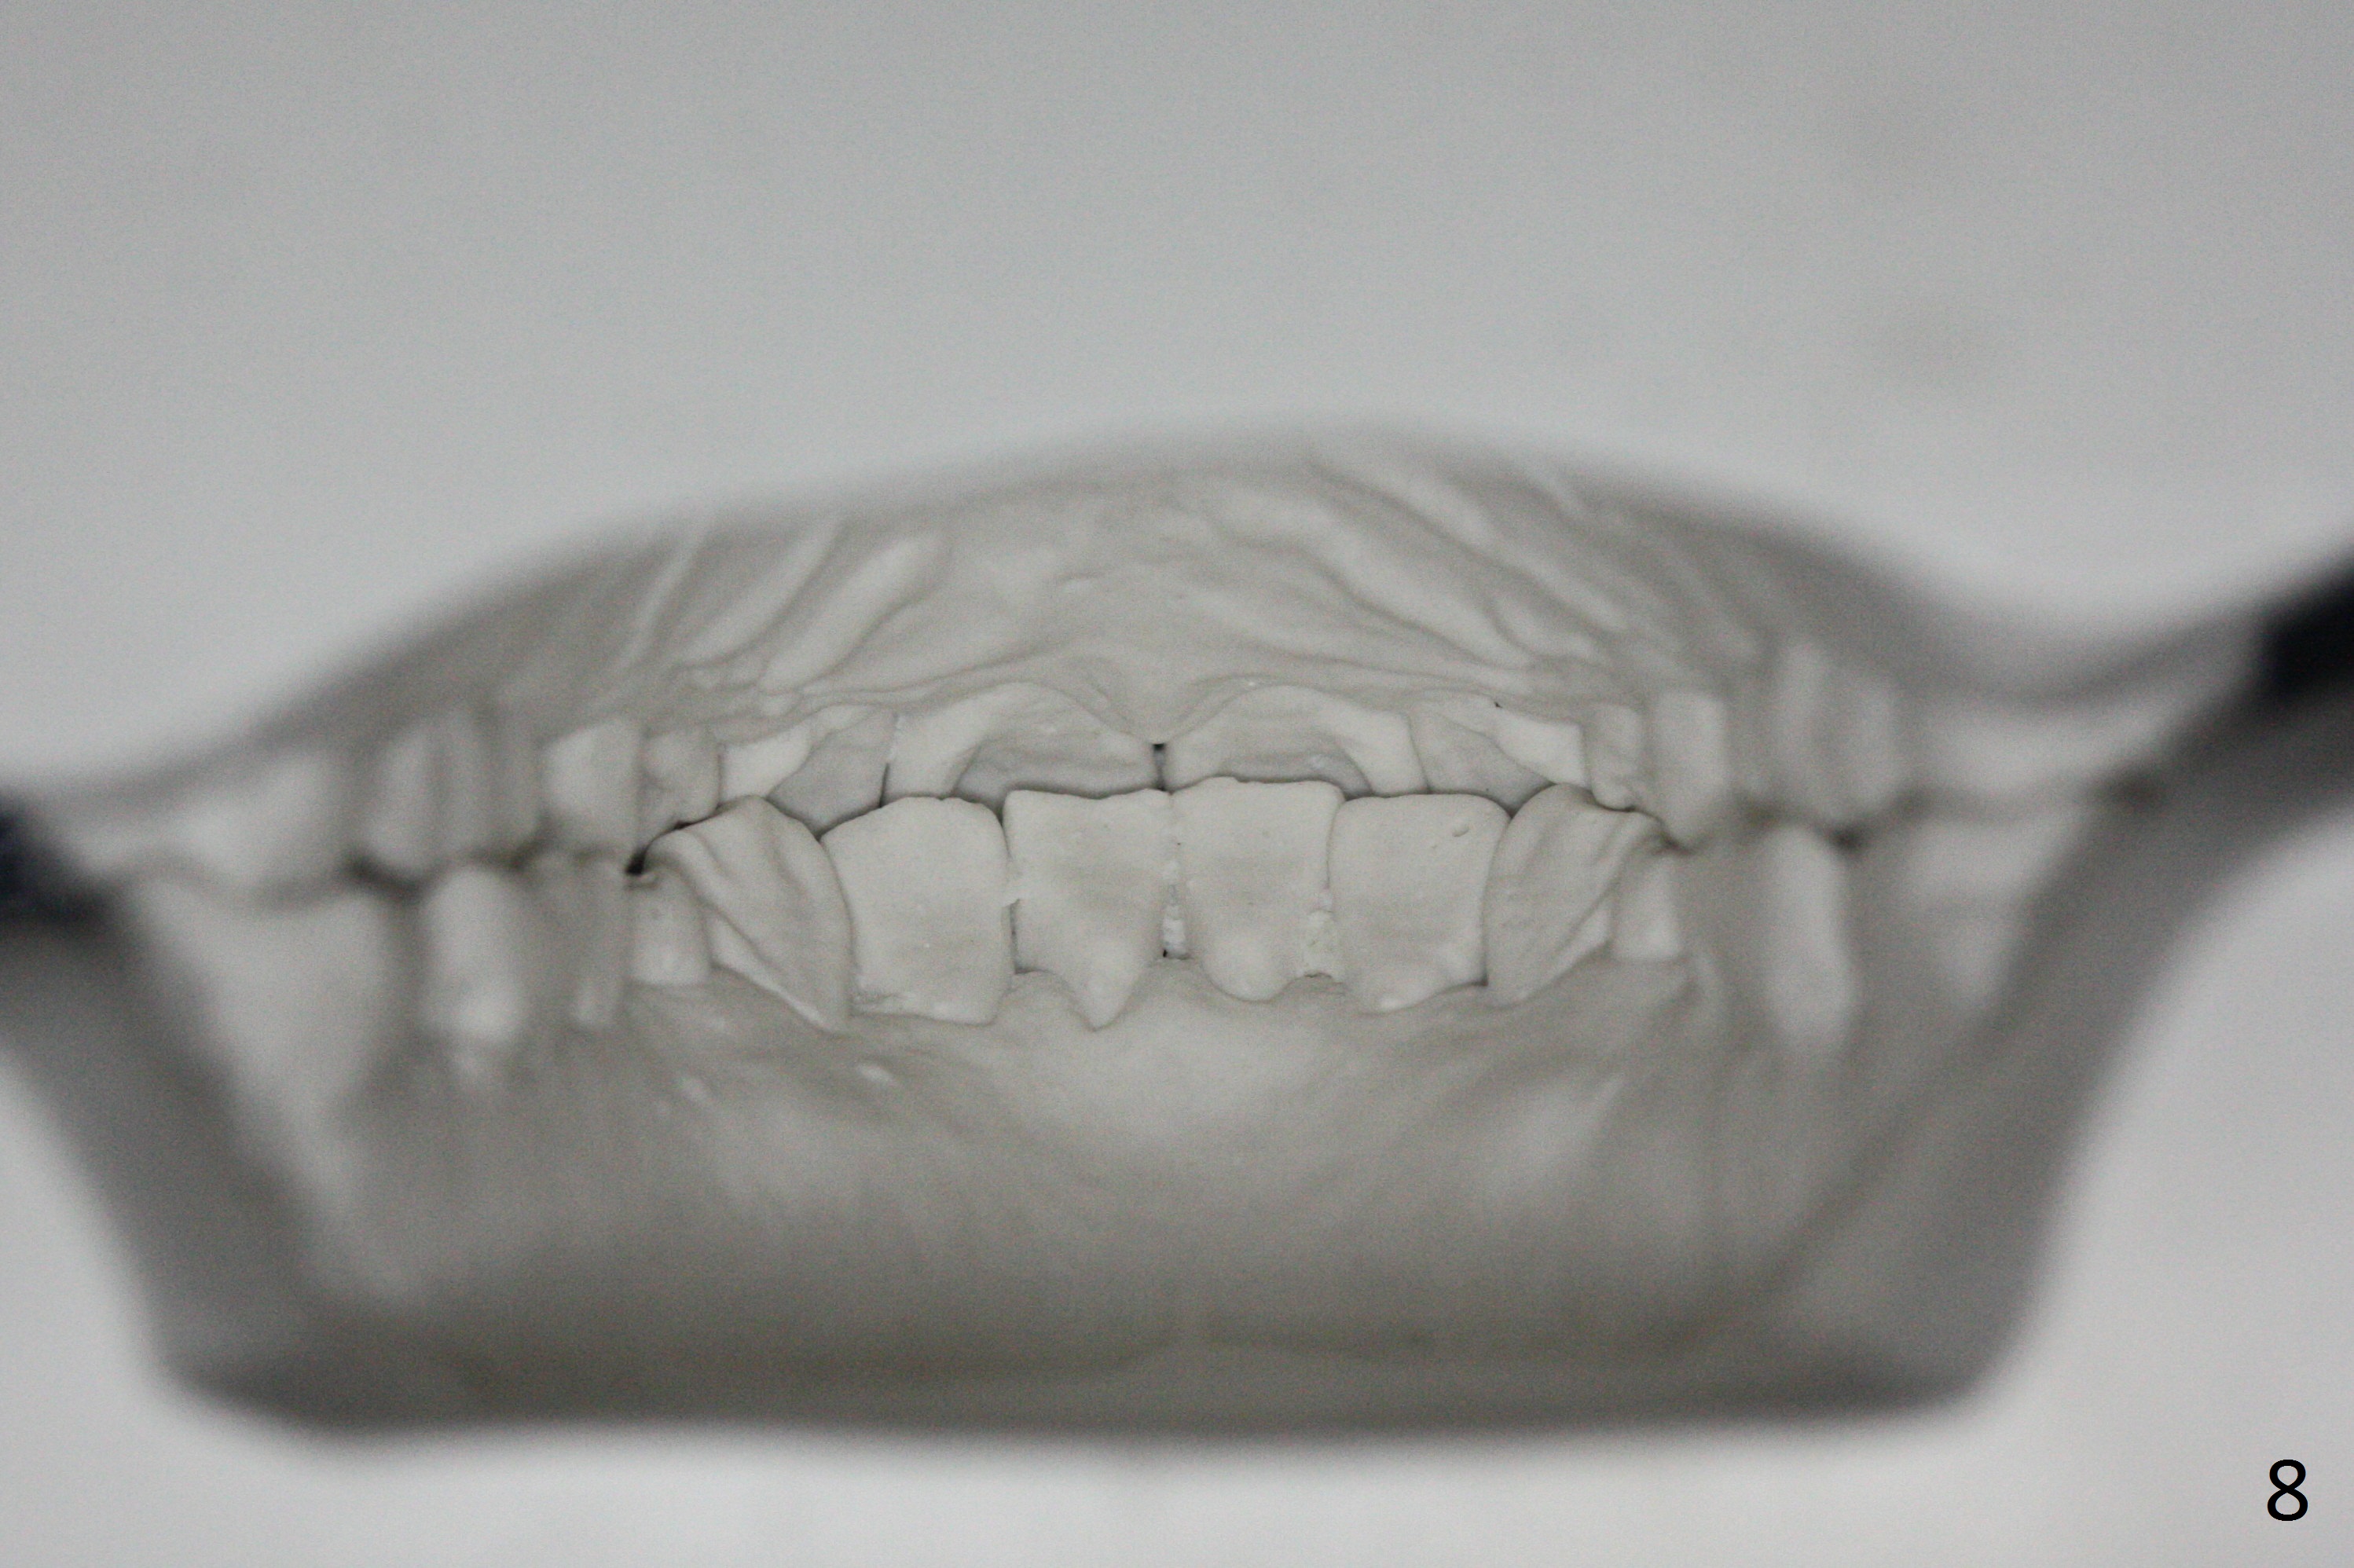

When orthodontic treatment is finished for a patient with crowding and anterior deep bite in 13 months, a diastema is found between the upper central incisors (Fig.2), which could be prevented by applying power chains for a few appointments prior to debanding. The upper anterior teeth look protrusive (Fig.4), proximal reduction seems necessary. Taking impression prior to debanding may reveal deficiency (Fig.5,6; 2nd good practice). The hidden diastemata can be revealed by use of 3-way syringe. The only prominent change is the reduction in the anterior deep bite (Fig.7,8 (posterior view)).